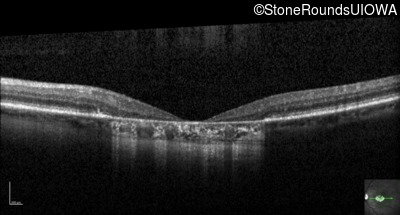

Optical Coherence Tomography - Left - 10/125 +1

Exemplar / OCT Stack